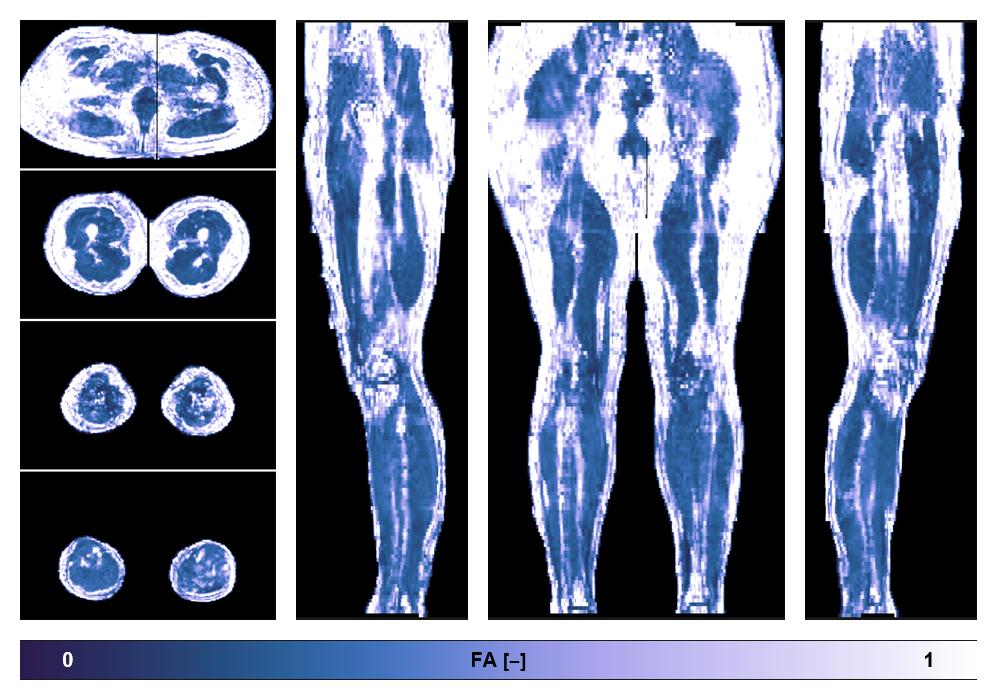

• Fractional anisotropy

IVIM corrected whole leg muscle fractional anisotropy obtained from diffusion tensor imaging.